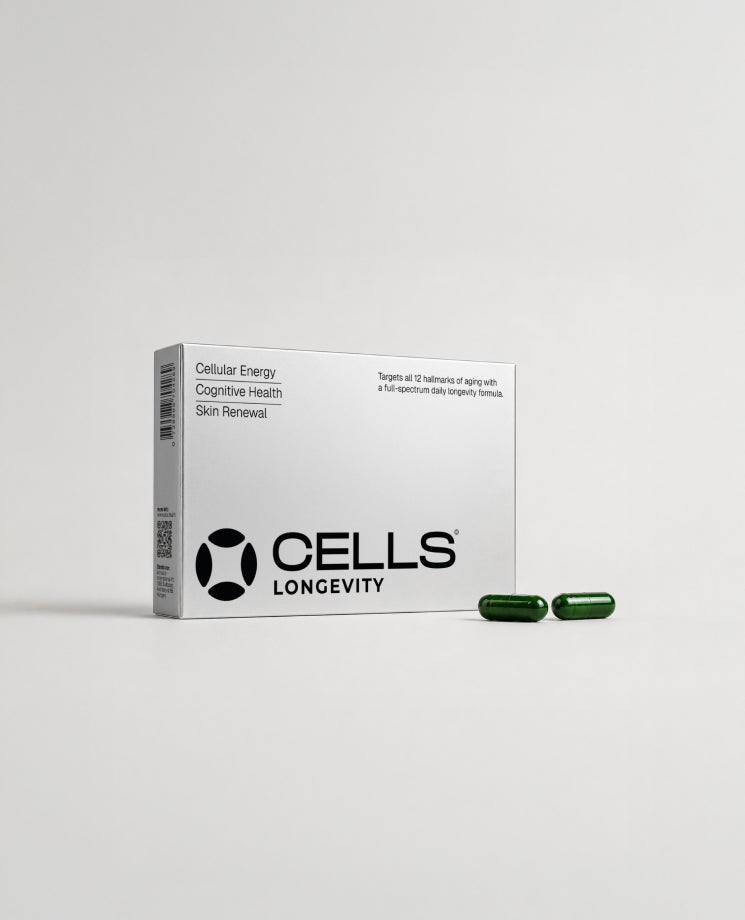

Backed by Biology. Designed for Daily Use.

Our scientists have carefully selected ingredients that can highly affect the 12 hallmarks of aging and looked at how ingredients work together to amplify their effectiveness.